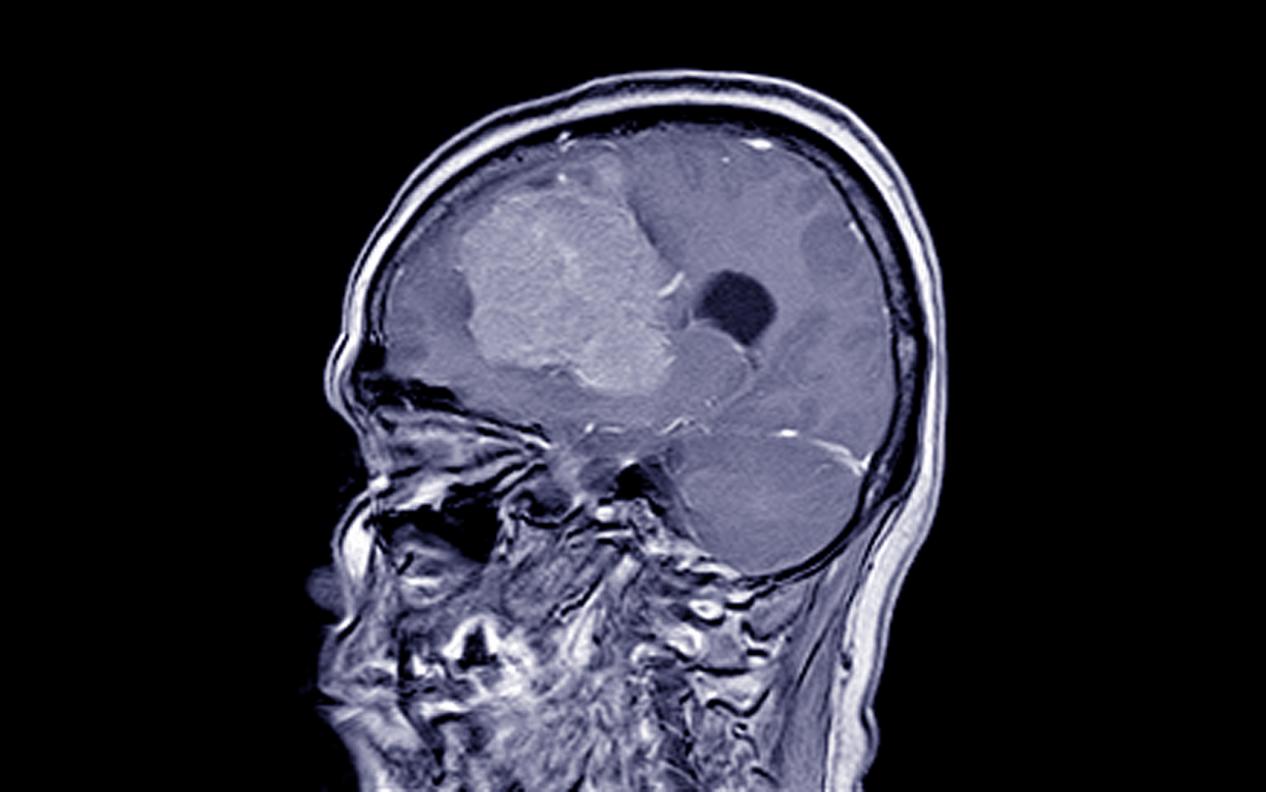

脑膜瘤的早期症状,昆明脑膜瘤医院推荐-昆明医科肿瘤医院脑膜瘤(Meningiomas)是起源于脑膜及脑膜间隙的衍生物,发病率占颅内肿瘤的19.2%,居第2位,女性:男性为2:1,发病高峰年龄在45岁,儿童少见。许多无症状脑膜瘤多为偶然发现。脑膜瘤是一种起源于脑...

脑膜瘤的临床表现,昆明脑膜瘤医院哪家好-昆明医科肿瘤医院脑膜瘤是一种常见的颅内肿瘤,它通常发生在脑膜(覆盖脑部和脊髓的薄膜)上。由于它的位置和生长速度不同,其症状和表现也会因个体差异而有所不同。但是,一些常见的症状和诊断方法可以帮助医生和患者及时发现和治疗脑膜...

昆明脑膜瘤放射治疗方式,昆明脑膜瘤医院哪家好-昆明医科肿瘤医院脑膜瘤(Meningiomas)是起源于脑膜及脑膜间隙的衍生物,发病率占颅内肿瘤的19.2%,居第2位,女性:男性为2:1,发病高峰年龄在45岁,儿童少见。许多无症状脑膜瘤多为偶然发现。脑膜瘤是指发...

脑膜瘤放射治疗医院,昆明脑膜瘤医院哪家好-昆明医科肿瘤医院脑膜瘤是一种发生在脑膜(脑部外层覆盖的薄膜)上的肿瘤。它通常是良性的,但在某些情况下也可能是恶性的。脑膜瘤的治疗通常需要一个综合治疗方案,其中包括手术切除、放射治疗和化疗。放射治疗是一种常用的治疗方法,...